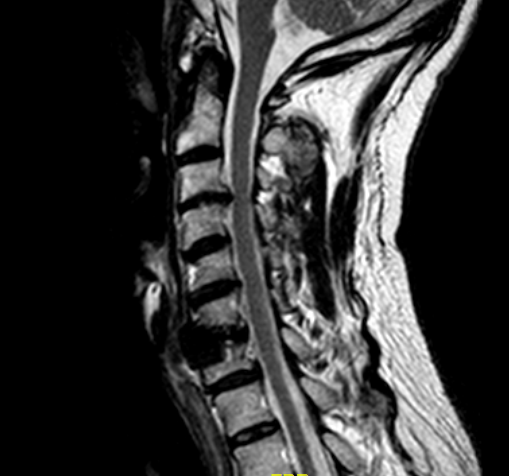

RM sagital T2.